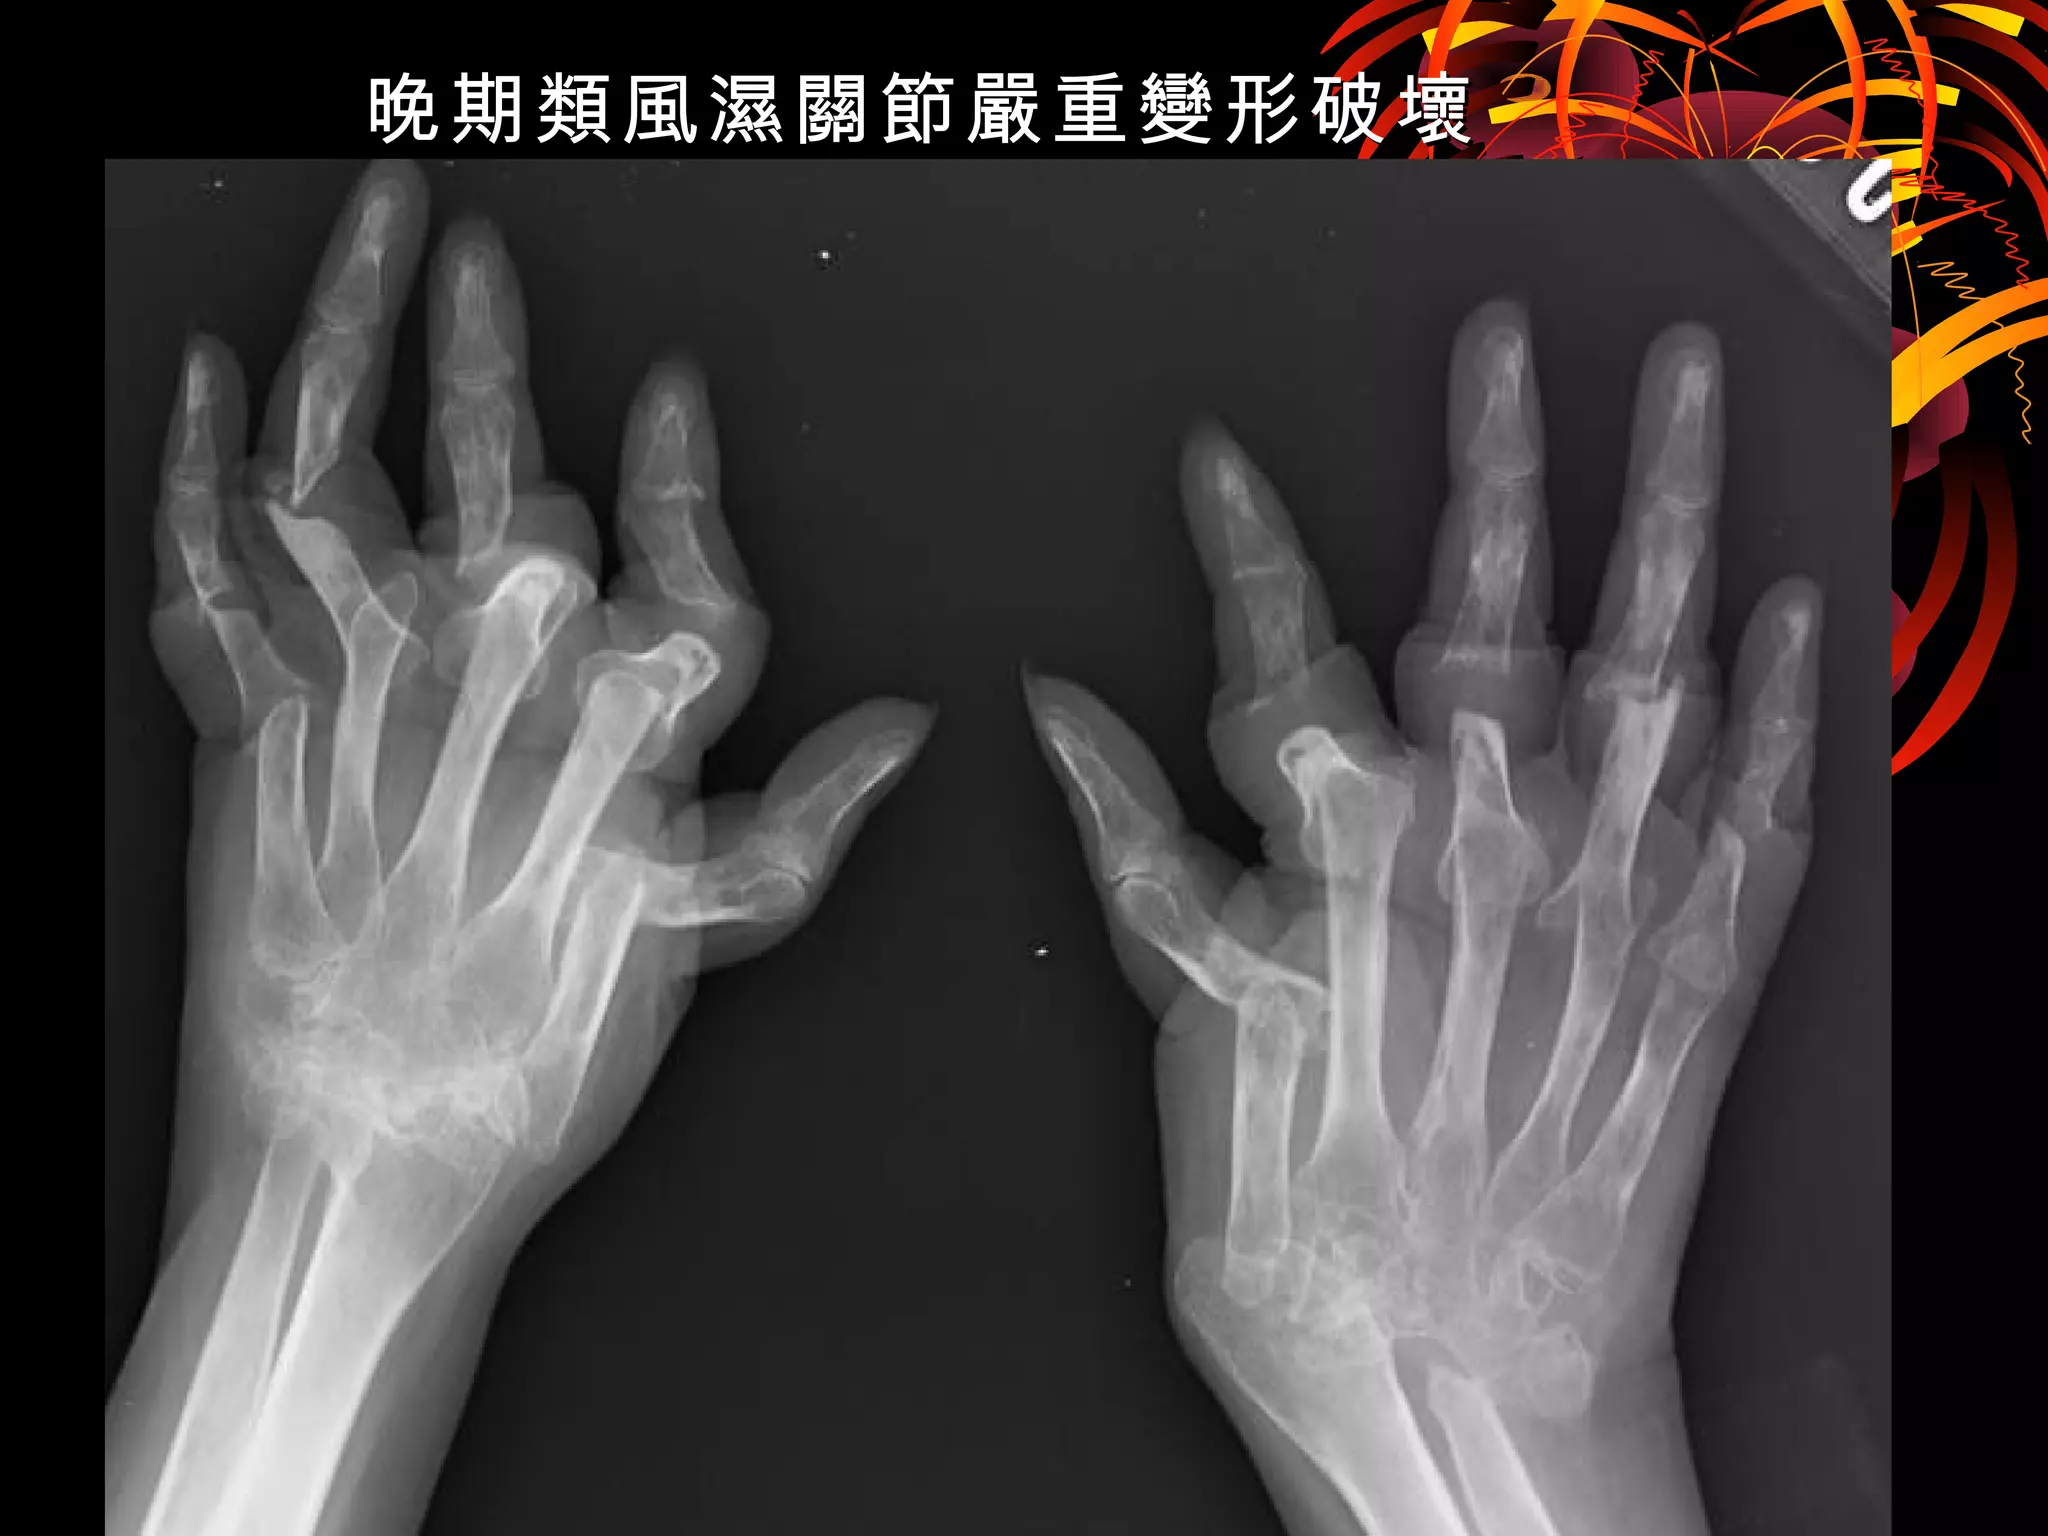

晚期類風濕關節嚴重變形破壞晚期類風濕關節嚴重變形破壞

類風濕關節炎的人生

死不了,活不好 ;

先 骨,後蝕心。啃

這就是類風濕 !

有了七個不同的生物製劑及達標治療

這樣的類風濕關節炎

永遠不該再出現任何一個臺灣人的雙手